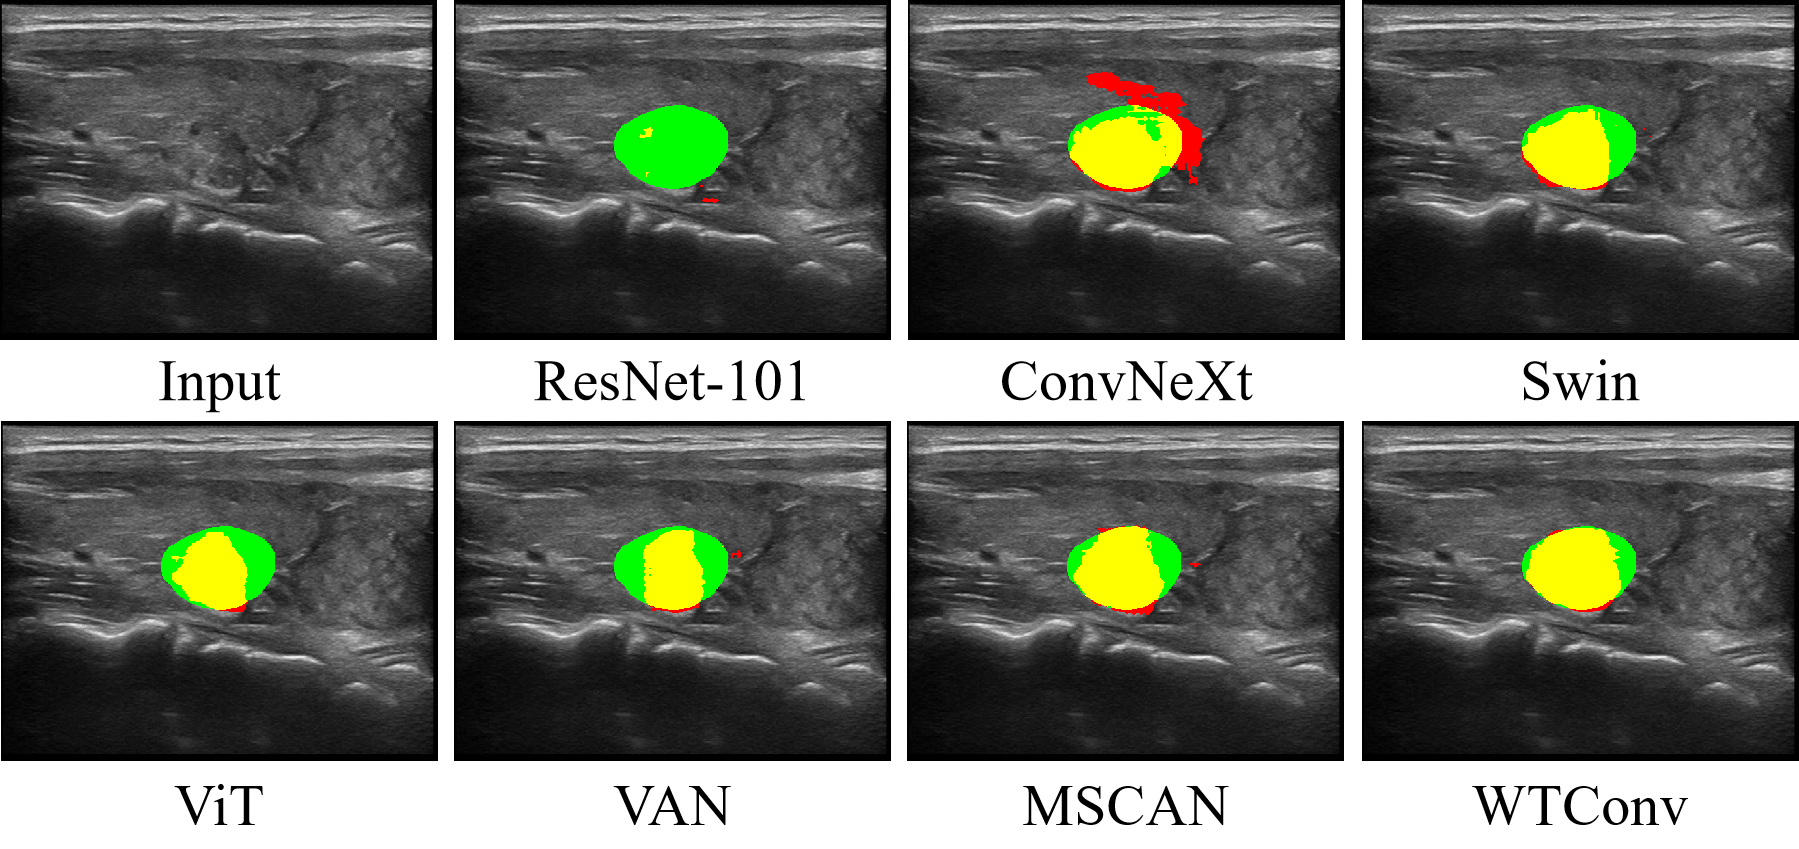

5.1 Comparison between WTConv backbone and SOTA backbones

The classical backbones with small version were selected for comparison with our proposed WTConv backbone, which was produced by removing the temporal fusion module from the MWConv encoder. The videos in the Thyroid Nodule dataset were split into individual frames that served as network inputs, and a comparison among the produced evaluation metrics is shown in Table 6. ConvNeXt and MSCAN, benefited from the small neighborhood convolution and the large receptive field of its kernels, achieving performance that was second only to that of our proposed method. Notably, the utilization of multiscale features by MSCAN yielded a marked improvement, motivating us to incorporate frequency-domain decomposition into our approach. In contrast, the ViT, Swin-T and VAN emphasize capturing long-distance dependencies, which limits their effectiveness at handling low-contrast ultrasound videos. Inspired by them, we integrate wavelet analysis theory into the convolution operation to increase its sensitivity to HF variations, improving detailed feature extraction without sacrificing the receptive field and facilitating the generation of multiresolution, multiscale feature representations. The visualization results of the comparison are shown in Fig. 6. Our predicted masks demonstrate the highest consistency with the ground-truth annotations and fewer false segmentation. This indicates the effectiveness of our method for accurately recognizing and segmenting small object boundaries. In summary, the experimental results indicate that WTConv backbone has the potential to be a generalized backbone for ultrasound image/video processing tasks.